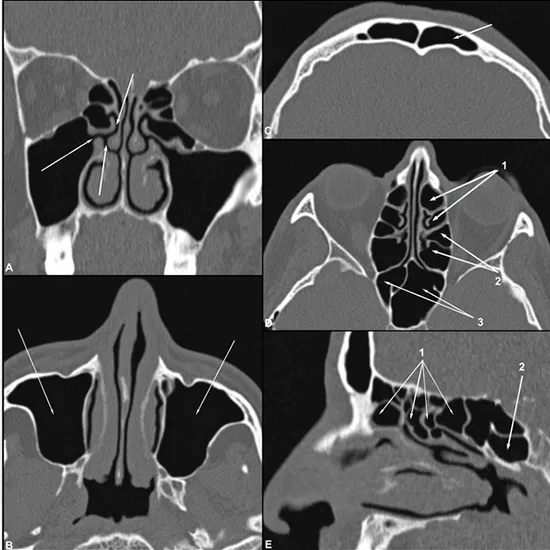

The paranasal sinus computerised tomography (PNS) test is used to detect disease of the paranasal sinuses, which are air-filled hollow spaces in the facial bones surrounding the nasal cavities. The test is used to diagnose diseases such as sinus birth defects, sinus infection in the bone, nasal polyps, sinusitis, sinus infection/inflammation, and sinus tumours. Using X-rays, this test quickly creates images of the sinuses. During the test, you may experience minor discomfort such as a burning sensation, a metallic taste in your mouth, and a warm flushing of the mouth, which is completely normal.

When Sinusitis or Post Nasal Drip (PND) is suspected, a doctor may order a CT PNS. Postnasal drip is the discharge of mucus from the sinuses and nose that can cause pinprick-like pain in the throat.